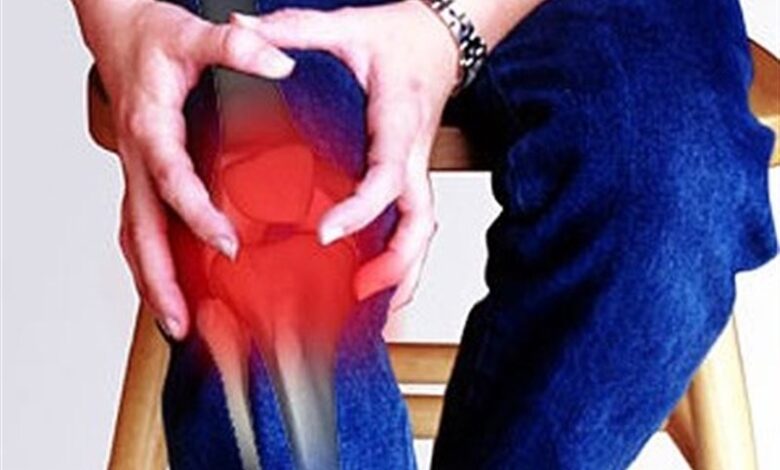

معاون درمان وزارت بهداشت با بیان این که آرتریت به عنوان یکی از شایعترین علل ناتوانی در جهان در بین سالمندان است، گفت: آرتریت بیماری مفصلی است که بعد از 30 سالگی به تدریج شیوع بیشتری پیدا میکند.